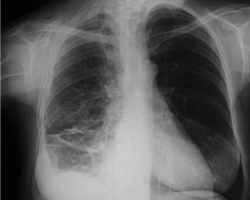

Femme de 65 ans

ATCD : tabagisme sevré, néo du sein droit traité par chirurgie et radiothérapie, exposition à l’amiante

Douleurs thoraciques droites + dyspnée d’effort + toux sèche

Abolition du murmure vésiculaire de la base droite + perte de poids